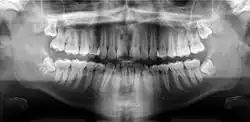

Un orthopantomogramme, abrégé par les sigles OPT ou OPG, est une radiographie panoramique de toute la denture. À ce titre, cet examen est plus souvent appelé « panoramique dentaire ».

Il consiste en une mise à plat de l'arc dentaire, d'une oreille à une autre.

Radiographie panoramique dentaire

Le cliché panoramique donne une vue d’ensemble des arcades dentaires, des maxillaires, des articulations et des sinus. Il est utilisé pour diagnostiquer un grand nombre de conditions pathologiques : infections, fractures des mâchoires, kystes et granulomes à la racine des dents, et certaines affections osseuses (maladie de Paget)…

On effectue aussi un panoramique dentaire pour évaluer la distribution des dents, la perte osseuse et les parodontites, ou encore pour visualiser l’ensemble des germes de dents chez l’enfant, pour définir son âge dentaire. Par ailleurs, il s’avère également utile pour décider du bien-fondé de la pose d’implants ou de la localisation des racines artificielles avant leur pose.